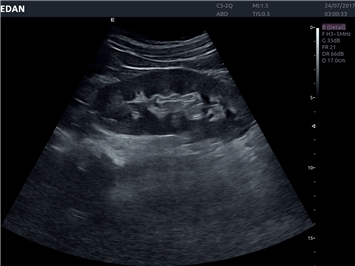

EDAN Acclarix LX4

Расширьте свои представления. Использование усовершенствованной платформой Acclarix система LX4 обеспечивает непревзойденную четкость изображений и интеллектуальный рабочий процесс для всех пользователей, являясь при этом наиболее экономичным решением.

EDAN Acclarix LX4 представляет собой инновационную ультразвуковую систему, построенную на усовершенствованной платформе Acclarix. Сочетание высокого качества визуализации с интеллектуальным рабочим процессом делает эту систему оптимальным выбором для клиник, ценящих эффективность и экономичность.

• Автоматизированные измерения в акушерстве

• Акушерства и гинекологии